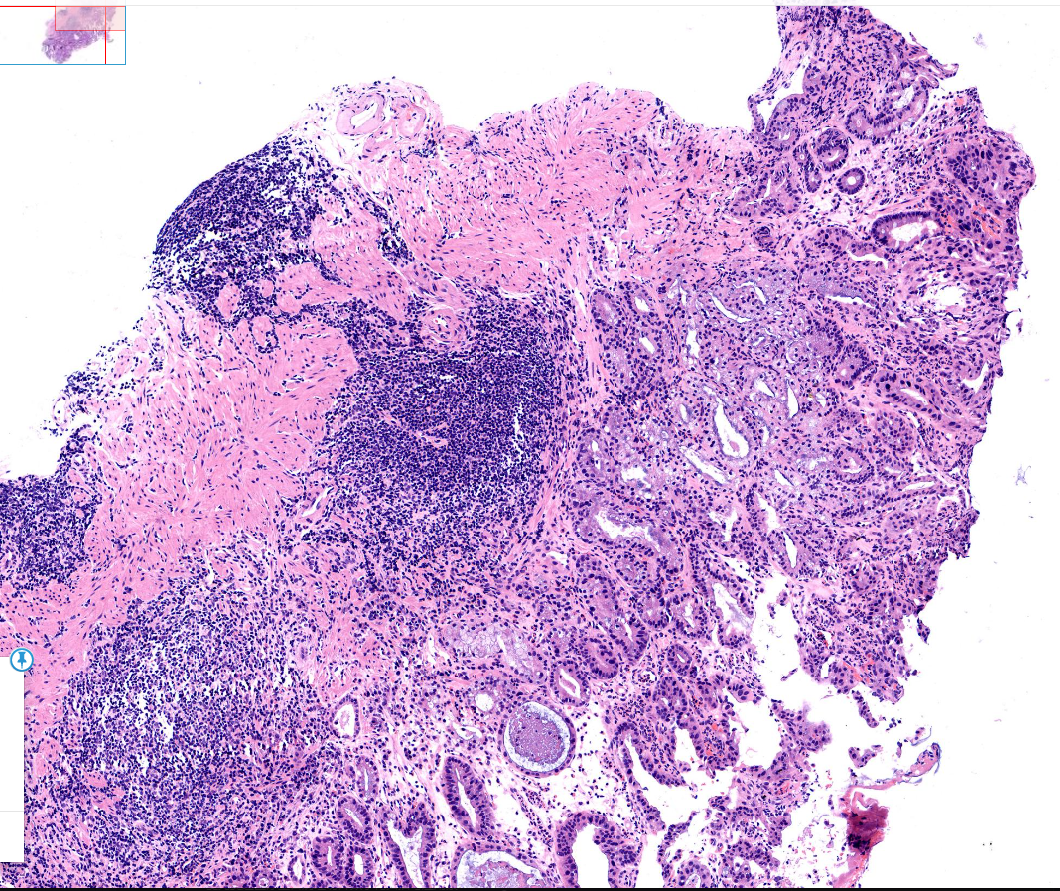

胃体活检

性别

男

年龄

77岁

临床诊断

一般病史

体检

标本名称

胃体

大体所见

胃体粘膜浅表凹陷

考虑为萎缩肠化伴糜烂部分腺体考虑为反应性修复性增生伴淋巴滤泡形成

有高级别上皮内瘤变

慢性萎缩性胃炎伴肠化,图4有高级别

早癌